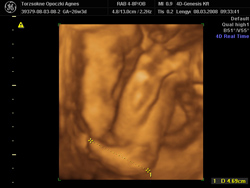

Melike, akkor ezek szerint jól tetted, hogy váltottál... én akkor tettem ezt, mikor megtudtam, hogy babát várok, és nagyon jó döntés volt. Ami az esküvőt illeti, az a legfontosabb, hogy nektek így tetszett. Mi mondjuk előre közöltük a szüleinkkel, hogy így lesz és kész, és ők el is fogadták... Máté nagyon aranyos a 4D-s fotókon!:)

Ibm, szuper fotók! Mi szerdán megyünk 4D-re, kiváncsi vagyok, ott mekkorának mérik majd Gábort... azért ez az 1150 gramm 25. hetesen kicsit megijesztett...

kis keze

kis keze

kis lába

kis lába